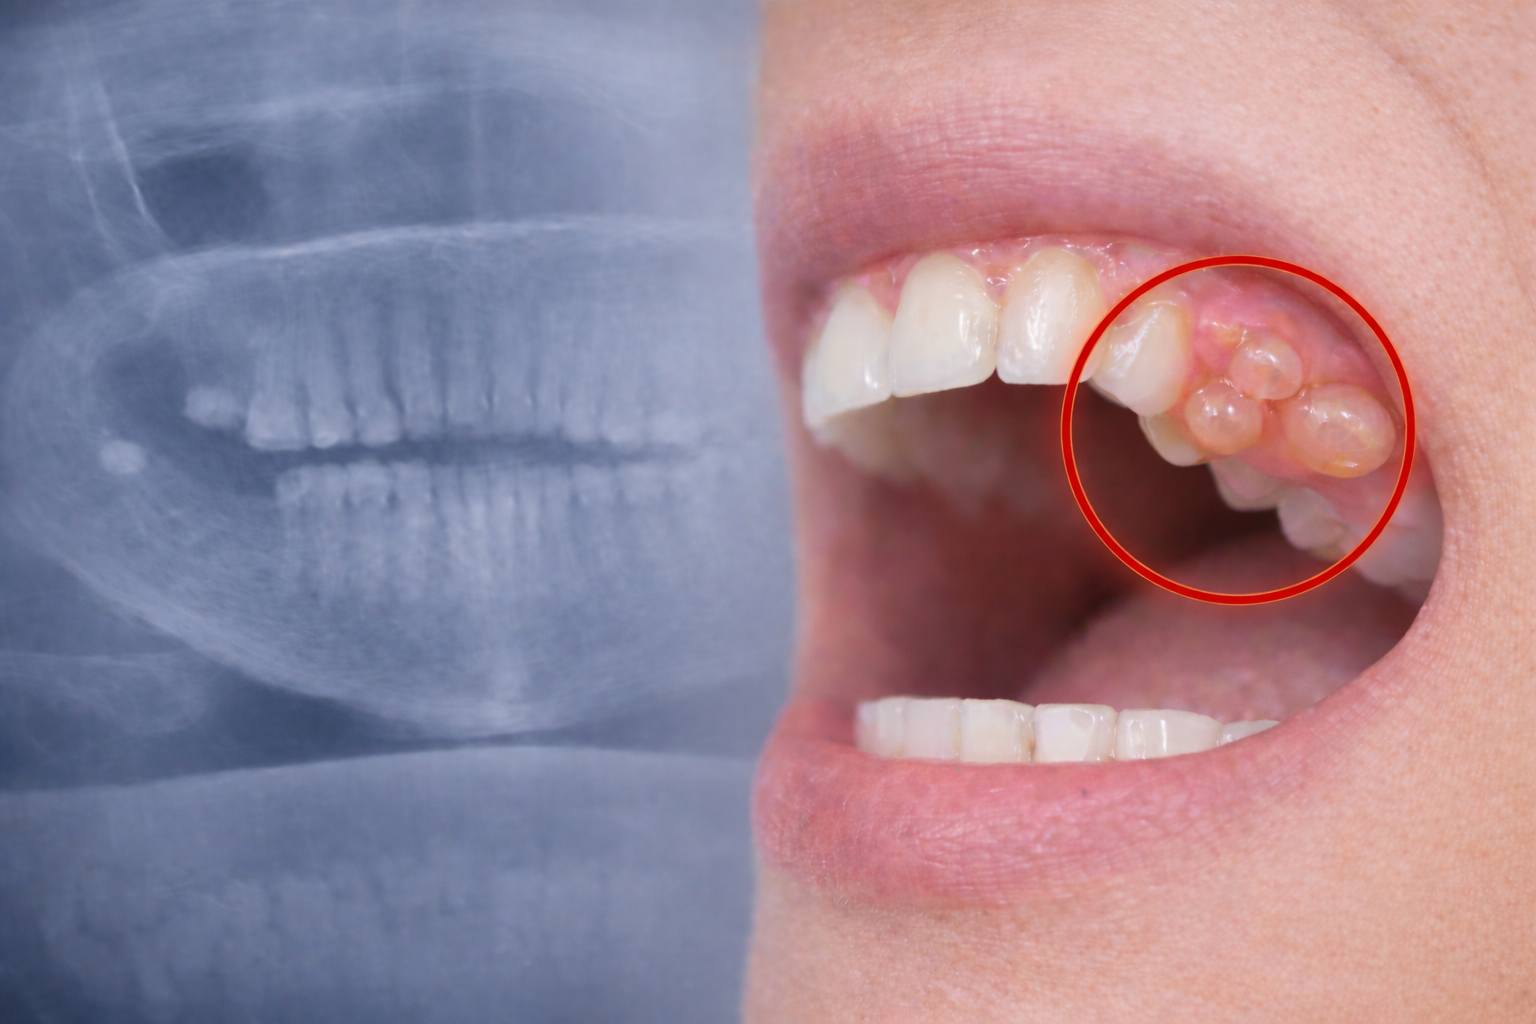

Benjolan di Gusi Tidak Sakit? Waspada Kista Gigi yang Bisa Merusak Tulang Rahang

Kista gigi adalah kantung berisi cairan atau jaringan patologis yang terbentuk di sekitar gigi, akar gigi, atau jaringan mulut.

Gejala Kista Gigi yang Sering Diabaikan

• Benjolan di gusi atau dalam mulut

• Tidak sakit (ini yang membuat banyak orang terlambat sadar)

• Kadang terasa penuh atau menekan

• Nyeri jika sudah terinfeksi

• Gigi terasa goyang tanpa sebab jelas

Sebagian besar kasus ditemukan secara tidak sengaja saat rontgen.

Studi di Indonesia menunjukkan hingga 10–18% pasien yang diperiksa ternyata memiliki kista dan banyak di antaranya tidak menyadarinya karena tidak menimbulkan rasa sakit.